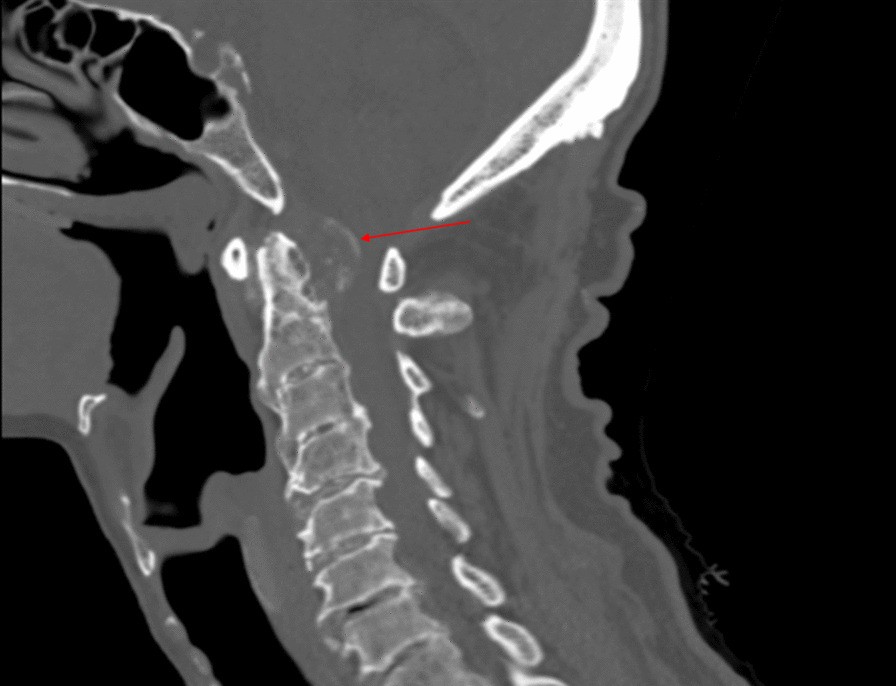

Fig. 1

From: Tophaceous gout of the atlantoaxial joint: a case report

Sagittal computed tomography of cervical spine revealing a large, retrodental calcific mass following the contour of the transverse ligament of atlas, causing severe spinal canal stenosis. The radiographic finding is highlighted by the arrow